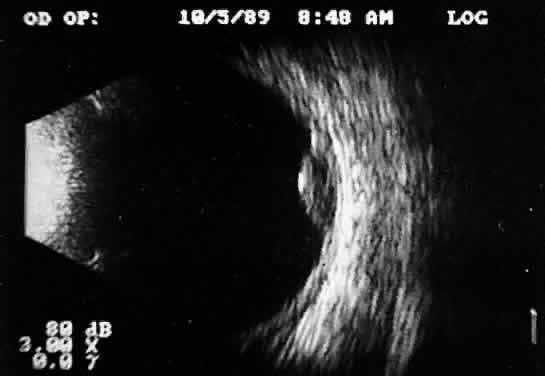

Ultrasound evaluation in patients with intraocular foreign bodies provides extremely useful additional information concerning associated ocular injuries and another method for localization, especially with nonmetallic intraocular foreign bodies not visible using x-ray techniques. Ultrasonically, foreign bodies have great reflectivity once the examining beam is placed perpendicular to a reflective surface of the foreign body. These abnormalities remain visible even with extreme attenuation of the examining signal (Fig. 16). Many metallic foreign bodies, especially those that are round or spherical, demonstrate “ringing,” a string of reflections that extend posterior to the foreign body in the form of a cometlike tail. Ringing is an ultrasound artifact produced by multiple “ping-pong” reflections of sound pulses within the foreign body before they return to the examining probe. The string of returning echoes produces an unusual display image.

Fig. 16. Contact B-scan and simultaneous A-scan: “buried” choroidal metallic foreign body. Note strong B-scan gray-scale image and high A-scan echo amplitude.